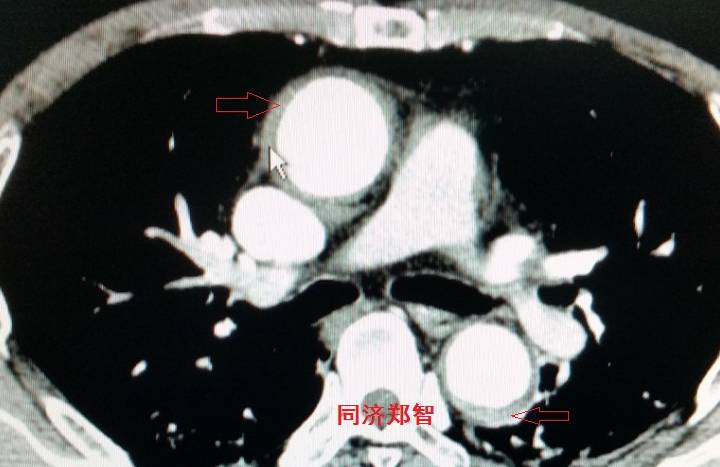

平扫CT提示主动脉弓层面及右肺动脉层面均可见主动脉血管腔内的内膜片影(红色箭头所示),CTA显示为A型主动脉夹层。

病例六

平扫CT提示降主动脉内膜片影(白箭头所示),CTA显示为B型主动脉夹层。